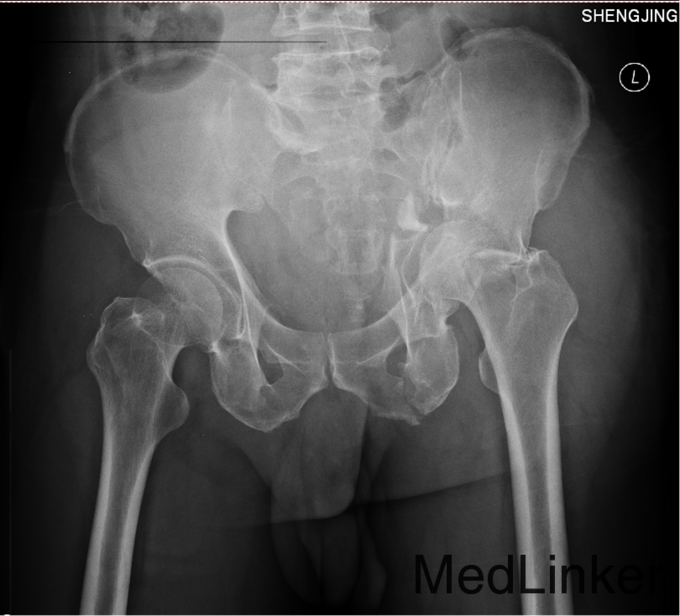

1.患者老年男性,以“车祸左髋部疼痛活动受限3天”为主诉入院。 2.现病史:患者自述于2014-11-04日晚下午7点发生机动车肇事,伤后患者急救车送往孤山二院,诊断为左髋臼骨折,当地医院未经任何治疗。急来中国医科大学附属盛京医院第五骨科创伤骨科治疗。我科以“左髋臼骨折”为主要诊断收入院。今来我院就诊,患者病来一般状态可,生命体征平稳,无发烧无发热,饮食睡眠可。

专科查体:患者平车入病房,左腿内收内旋屈曲畸形,左髋部压痛(+),叩击痛(+),骨盆分离试验阳性,活动受限,双下肢感觉未见异常,活动可,双侧足背动脉搏动可触及,双侧足趾活动灵活。